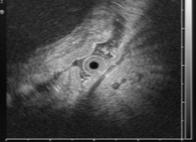

Ранний рак желудка. Общий эндосонографический критерий всех типов раннего рака желудка – это очаг неоднородного гипоэхогенного образования в пределах только слизистого слоя или занимающий слизистый и подслизистый слои стенки желудка (рис.1).

Рис.1. 62 года. Ранний рак верхней трети тела желудка.

Гистология – высокодифференцированная аденокарцинома:

а - визуальная картина РРЖ, подтип IIa; б – эндосонограмма РРЖ, подтип IIa, гипоэхогенное образование с признаками инвазии опухоли в подслизистый слой.